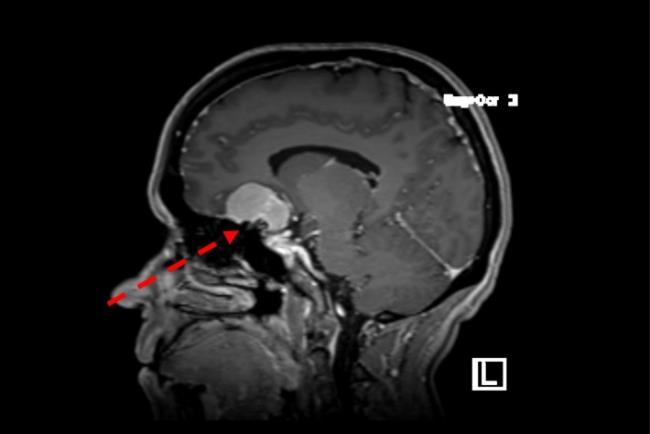

גידול של בלוטת יותרת המוח מסוג מאקרואדנומה היפופיזרית בגבר בן 30 אשר התלונן על הידרדרות מתמשכת בראייה. נותח בגישה טרנס ספנוידלית דרך האף (קו מקווקו ירוק) לכריתה מלאה של הגידול.

כאמור, במקרים רבים בהם התגלה גידול בבלוטת יותרת המוח לא יהיה צורך בטיפול. עם זאת במצבים בהם הגידול הוביל לפגיעה בהפרשה ההורמונלית, בראייה, או שגרם לסימפטומים שונים יהיה צורך לבצע ניתוח להסרת הגידול.בעשור האחרון, ניתוחים להסרת גידולי היפופיזה מתבצעים בגישה טרנס-ספנואידלית אנדוסקופית (TSS). כלומר, הגישה לבלוטה מתבצעת דרך חלל האף והסינוס הספנואידלי – חלל ריק המהווה חלק ממערות פנים. גישה אנדוסקופית זו מאפשרת חשיפה טובה יותר של הגידול ותוצאות ניתוחיות טובות יותר.